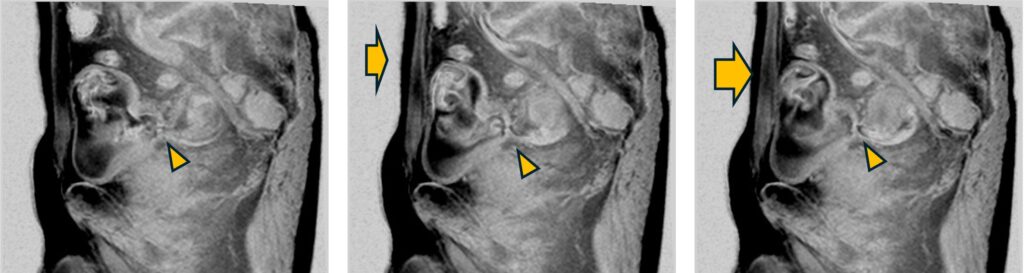

・尿管瘤

自由呼吸下で撮像すると、腹壁の動き(→)に同期した尿管と膀胱間(△)のジェット流が観察され、閉塞性でないことを確認できます。